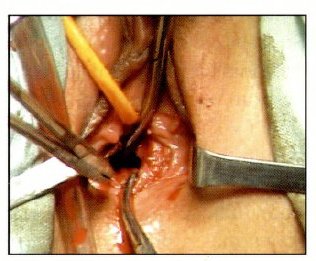

Durante el acto quirúrgico se realizo una incisión trasversal a nivel del fondo de saco vaginal separando la capa mucosa y la fascie vesicouterina, se incidió en los tejidos perineales por divulsión, teniendo como guía un dedo en el recto por atrás y la sonda Foley por delante para delimitar la uretra y el recto respectivamente, una vez atravesado la parte superior del tabique se completa la incisión transversal en todo el ancho de la cavidad vaginal que corresponde a las cuatro paredes de la vagina.

Se drena 1000 cc de liquido de color achocolatado que corresponde a tejido menstrual retenido; se realiza un lavado exhaustivo de la cavidad vaginal mas la colocación de puntos en la mucosa y la fascie vaginal de ambos extremos, proximal y distal, dejando un orificio aceptable de 2 cm. de diámetro; se coloca un tapón vaselinado, que se retira al día siguiente; manteniéndose con soluciones parenterales por 24 horas y antibióticoterapia por 7 días, fue dada de alta al tercer día con evolución favorable e indicación de dilatación diaria con su dedo medio lubricando con bacitracina en crema (Fig: 5, 6, 7, 8).

Fig 6: Apertura de Tabique